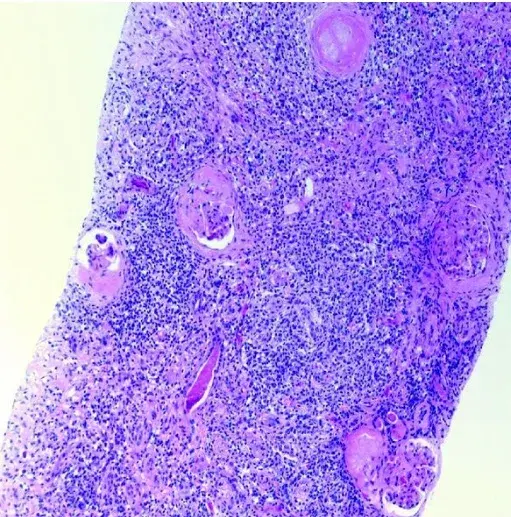

Proteinúria refratária em paciente com Nefrite Lúpica

Proteinúria refratária em paciente com Nefrite Lúpica